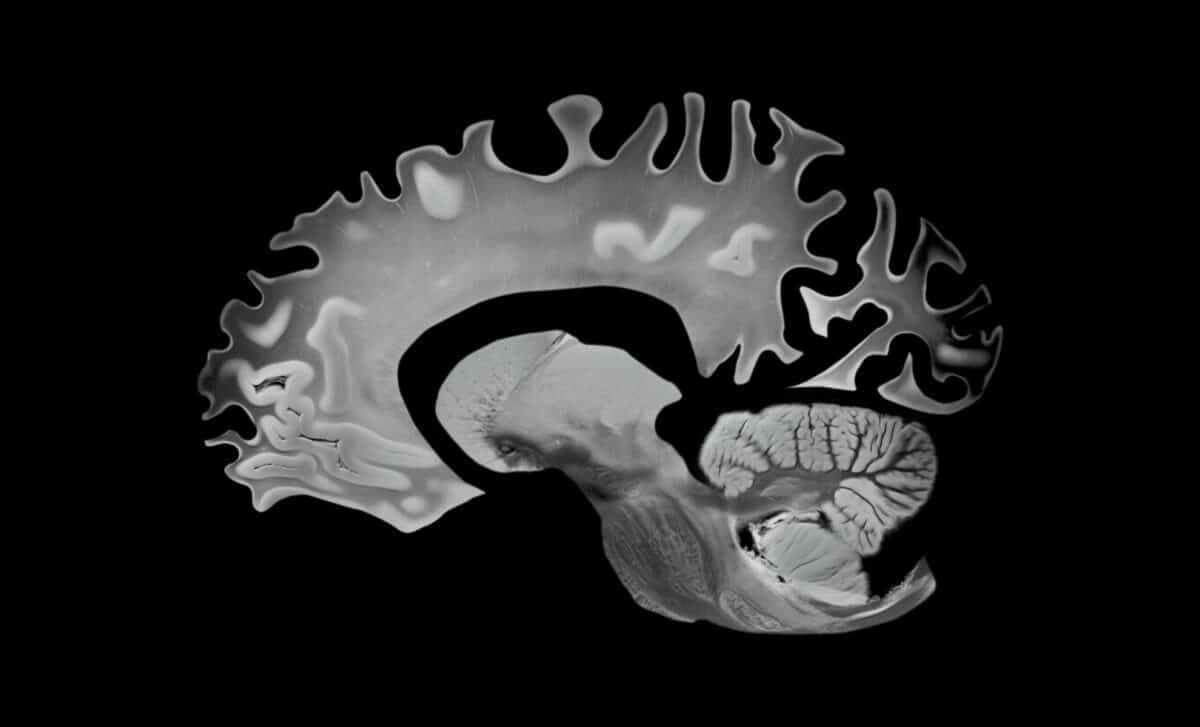

This "Hybrid" Diet Doesn't Just Protect Your Heart, It's Slowing Brain Aging Too

A decade-long study of 1,600 adults just revealed a diet that measurably slows brain aging. The findings may change everything.